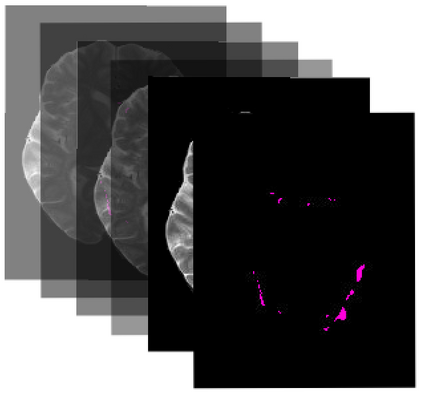

Many automatic machine learning models developed for focal pathology (e.g. lesions, tumours) detection and segmentation perform well, but do not generalize as well to new patient cohorts, impeding their widespread adoption into real clinical contexts. One strategy to create a more diverse, generalizable training set is to naively pool datasets from different cohorts. Surprisingly, training on this \it{big data} does not necessarily increase, and may even reduce, overall performance and model generalizability, due to the existence of cohort biases that affect label distributions. In this paper, we propose a generalized affine conditioning framework to learn and account for cohort biases across multi-source datasets, which we call Source-Conditioned Instance Normalization (SCIN). Through extensive experimentation on three different, large scale, multi-scanner, multi-centre Multiple Sclerosis (MS) clinical trial MRI datasets, we show that our cohort bias adaptation method (1) improves performance of the network on pooled datasets relative to naively pooling datasets and (2) can quickly adapt to a new cohort by fine-tuning the instance normalization parameters, thus learning the new cohort bias with only 10 labelled samples.